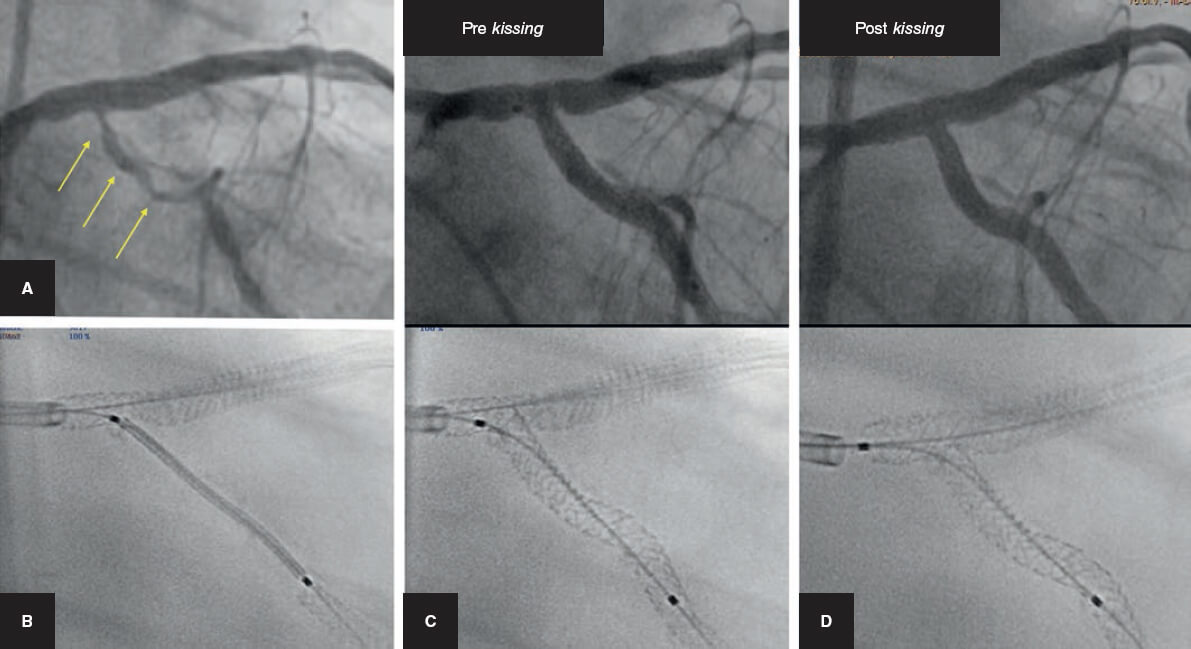

Técnica de la guía encarcelada

La estrategia del stent provisional se ha llamado «técnica simple», aunque en ocasiones puede no ser tan simple porque la RL puede ocluirse tras el implante del stent en el VP (figura 3). Esta situación, si no se resuelve, conduce a un infarto de miocardio. La técnica de la guía encarcelada se describió para ayudar a resolver esta situación. Consiste en dejar una guía en la RL mientras se implanta el stent del VP. De esta forma queda atrapada entre la pared del vaso y la estructura metálica del stent.

Figura 3. Cuatro ejemplos de oclusión abrupta de la rama lateral tras el implante del stent en el vaso principal. A y B: descendente anterior/diagonal. C: coronaria derecha/descendente posterior. D: tronco común de la coronaria izquierda con cierre de la arteria circunfleja.

Las ventajas que proporciona son:

La guía encarcelada ayuda a mantener abierta la RL, y en caso de oclusión de esta, la guía es el único marcador de su posición, lo que posibilita el rescate del vaso ocluido.

Facilita el acceso a la RL al modificar favorablemente el ángulo de la bifurcación.

Produce un mecanismo de anclaje de la guía, y así facilita la intubación del catéter guía al suministrar un apoyo más firme para cruzar el origen de la RL con el balón.

Por último, en situaciones extremas, puede utilizarse para introducir un balón de bajo perfil, dilatar la RL y terminar con la técnica de inverted crush o redilatando el stent aplastado en el VP una vez que se ha resuelto la oclusión de la rama9.

Riesgos de la técnica de la guía encarcelada. Dado que el stent del VP queda impactado a presión contra la pared arterial, la guía atrapada entre estas 2 estructuras puede sufrir daño e incluso fracturarse en el momento de su retirada10. A pesar de que es un hecho infrecuente, se han descrito casos de rotura de la guía al realizar su extracción; una grave complicación del procedimiento que en ocasiones requiere una extracción quirúrgica de urgencia11-13. Existen algunas recomendaciones para prevenir la fractura de la guía14: a) no ubicar la porción distal de la guía en vasos secundarios de escaso calibre; b) evitar las altas presiones en la suelta del stent; c) evitar cubrir una gran porción de la guía encarcelada con varios stents; y d) usar el tipo de guía más resistente a la tracción. Este último punto ha generado mucha controversia en los últimos años. Así, inicialmente se recomendó el uso de guías no poliméricas basándose en opiniones de expertos15,16, pero cuando se realizó un estudio aleatorizado para evaluar el daño de la guía tras su encarcelamiento por microscopía estereoscópica resultaron más resistentes y con menos daño las guías poliméricas10. No obstante, las nuevas generaciones de guías también deberían probarse para esta indicación.